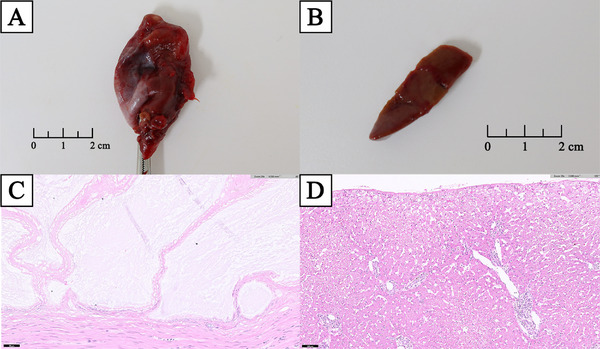

Histopathological analyses of the excised gallbladder and liver biopsy samples were performed (Figure 3A,B). The gallbladder showed hyperplastic mucosal proliferation and multifocal mucosal ulceration, which is consistent with ruptured GBM (Figure 3C). The liver showed lymphoplasmacytic and neutrophilic hepatitis, multifocal bile plug formation, bile stasis, biliary proliferation and intrahepatocytic pigmentation, with extensive neutrophilic and fibrinous peritonitis (Figure 3D).